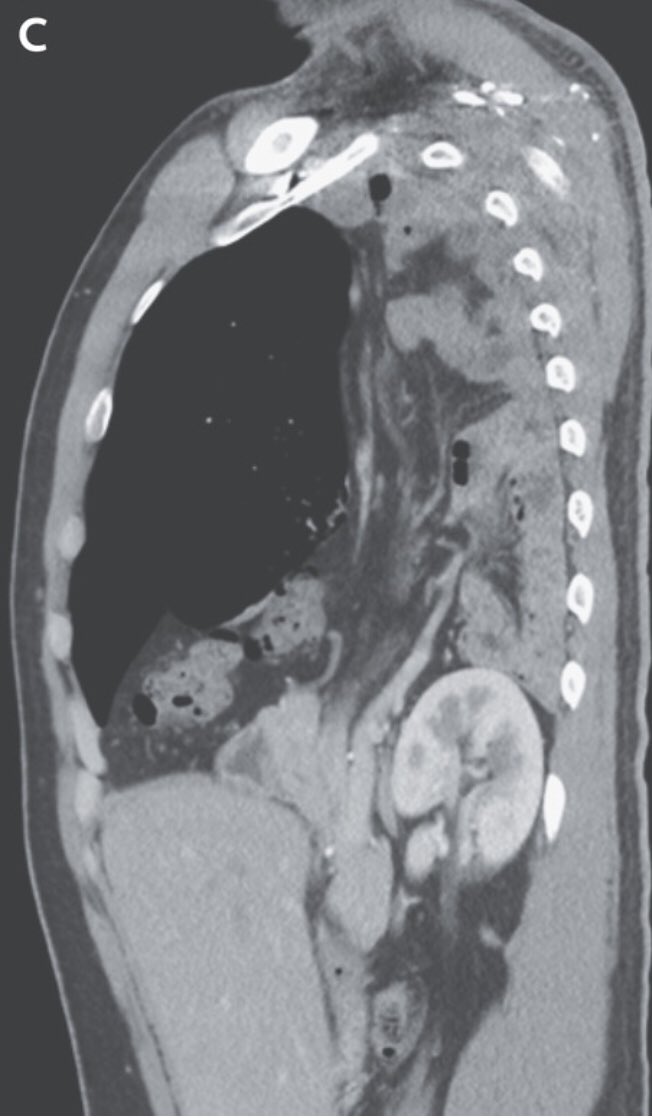

و النص اليمين من الحجاب الحاجز طالع لفوق شوية جهة الصدر (elevated right hemidiaphragm)

القولون كان قاعد في فوق في محل ما محلو (translocation of the colon into the right upper quadrant of the abdomen)

و السبب هو عيب خُلقي في الحجاب الحاجز

التشخيص الإتعمل للشاب دا هو انو عندو فتق بوكدالك، او فتق حجابي خلقي

congenital diaphragmatic hernia due to a posterolateral diaphragmatic defect-Bochdalek hernia

في العادة العيانيين بيتعرفو و بيتشخصو صغار عشان الاعراض البيعملها الفتاق

في حالات نادرة ممكن تكون من غير اعراض و المريض يكبر بيها و عندها العرض الممكن يجي بيه العيان هو انسداد معوي